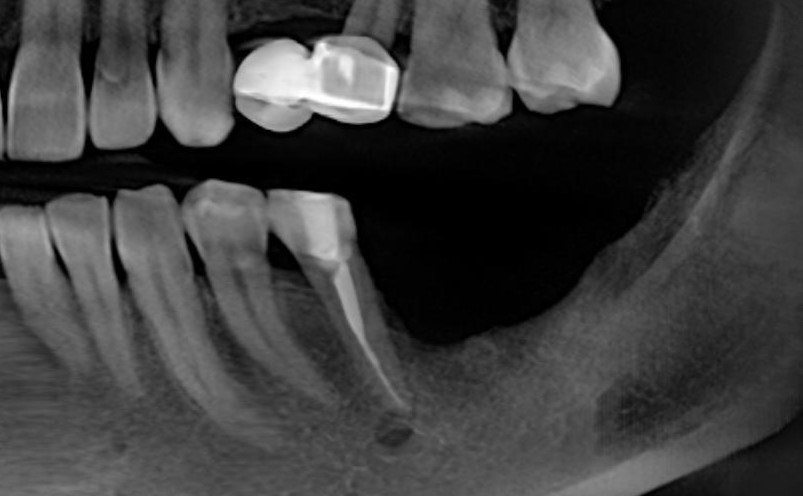

После операции:

— контрольный снимок (раньше делали ОПТГ, сейчас — строго КЛКТ)